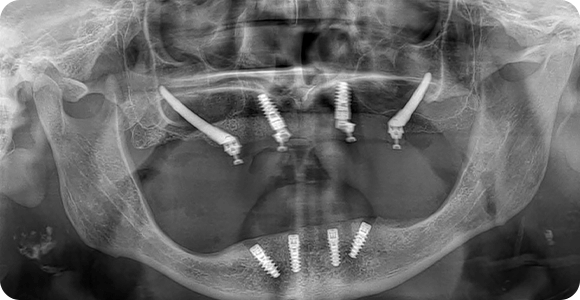

Öncesi & Sonrası